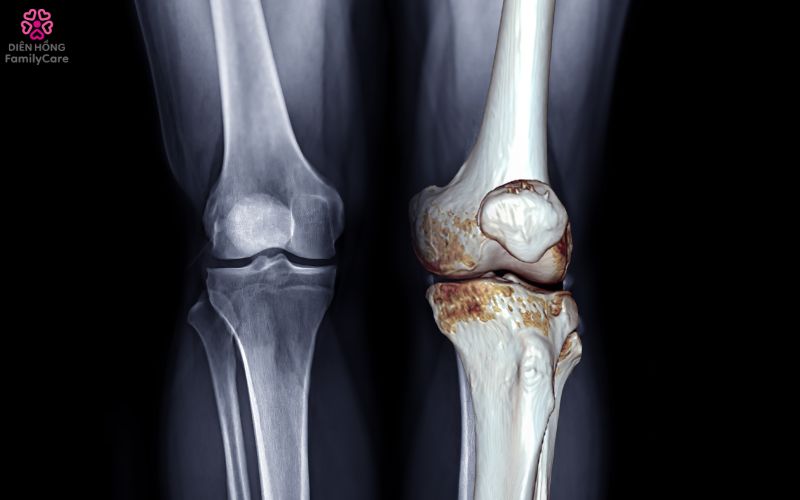

Khớp kêu lạo xạo khi vận động: Đây là dấu hiệu sụn khớp bị bào mòn, bề mặt khớp cọ xát nhau.

Sưng, biến dạng khớp: Ở giai đoạn muộn, khớp có thể sưng, lệch trục, gây hạn chế vận động nặng nề.

📌 Nếu người cao tuổi có nhiều dấu hiệu trên, nên đi khám sớm để được chẩn đoán bằng X-quang, MRI hoặc siêu âm khớp.